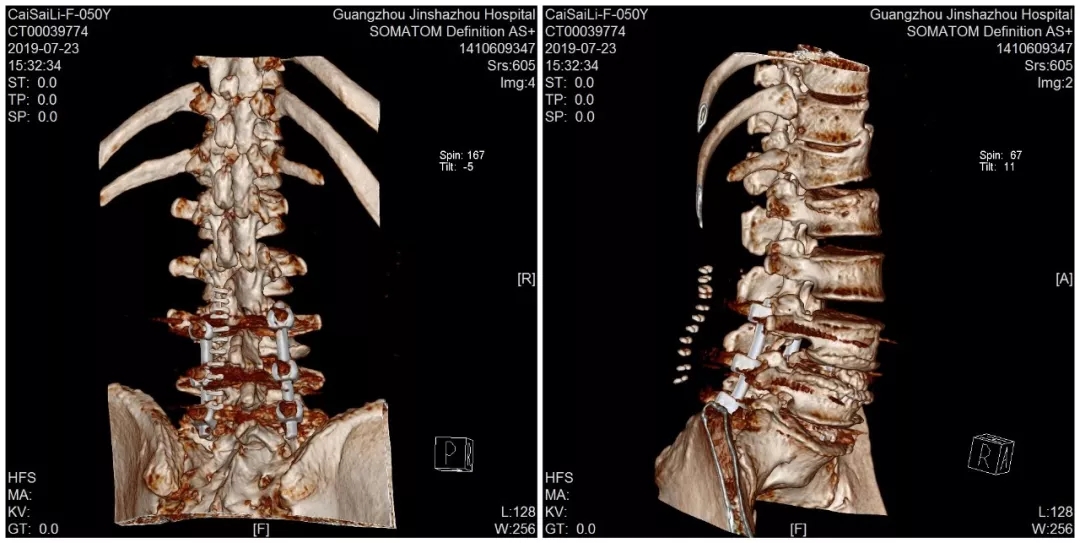

术后CT三维重建

于是经朋友介绍,蔡阿姨来到了我们金沙洲医院骨科中心求诊。经检查提示腰2椎体压缩性骨折,腰椎峡部裂。由于蔡阿姨的骨折和腰椎突出情况比较复杂,经过对蔡阿姨病情的详细评估,骨科中心分二次给蔡阿姨进行了手术。在我们见到蔡阿姨的时候,她第二次手术已经结束,除了下肢尚有一点点麻痹,医生说她其他方面恢复得很好,她看起来精神也不错。